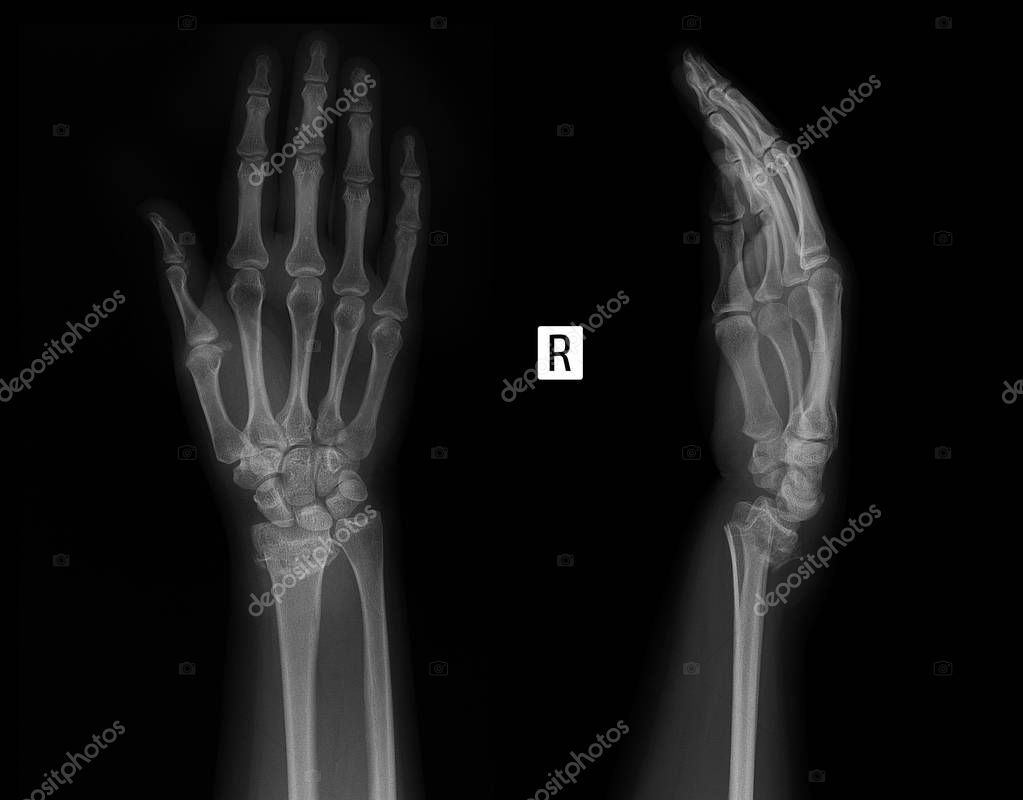

Рентгенограмма при переломе дистального эпиметафиза лучевой . . .

Перелом лучевой кости в типичном месте . Переломы лучевой кости выше лучезапястного сустава считаются самыми распространенными травмами костей предплечья . В основе травмы лежит сочетание перелома луча с вывихом локтевой кости в лучезапястном суставе .

Перелом луча в типичном месте . «Типичный» луч? Переломы дистального метафиза лучевой кости являются одной из наиболее распространённых травм в практике травматолога ортопеда . И как это часто бывает с часто встречающейся травмой, многие аспекты, как самого . . .

• Перелом Смита (обратный перелом Коллиса): о Поперечный перелом дистального метафиза лучевой кости о Ладонное угловое отклонение крупного дистального отломка (увеличение нормального ладонного наклона) о Плотность костей обычно нормальная .

Самым частым травматическим повреждением костей верхних конечностей является перелом луча в типичном месте . Нарушение целостности нижнего конца лучевой кости, расположенного в непосредственной близости с кистью, считается несложной травмой .

Перелом лучевой кости в типичном месте — как раз такая травма, при Иммобилизацию локтя при переломах лучевой кости в типичном месте можно считать «пережитком Через 7-10 дней обязательно необходимо выполнить контрольные рентгенограммы лучезапястного сустава, т .к . . .